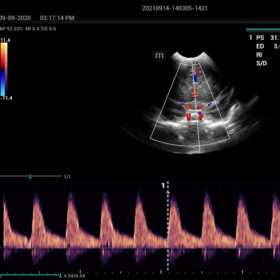

- HR-Flow Improving the hemodynamic presentation

Cardiovascular Solution

- Auto EF– Automatic measurement of ejection fraction by diastole/systole frames

- TTQA-Myocardial sychronization evaluation with quantitive analysis

- RIMT-RF data based real-time IMT measurement